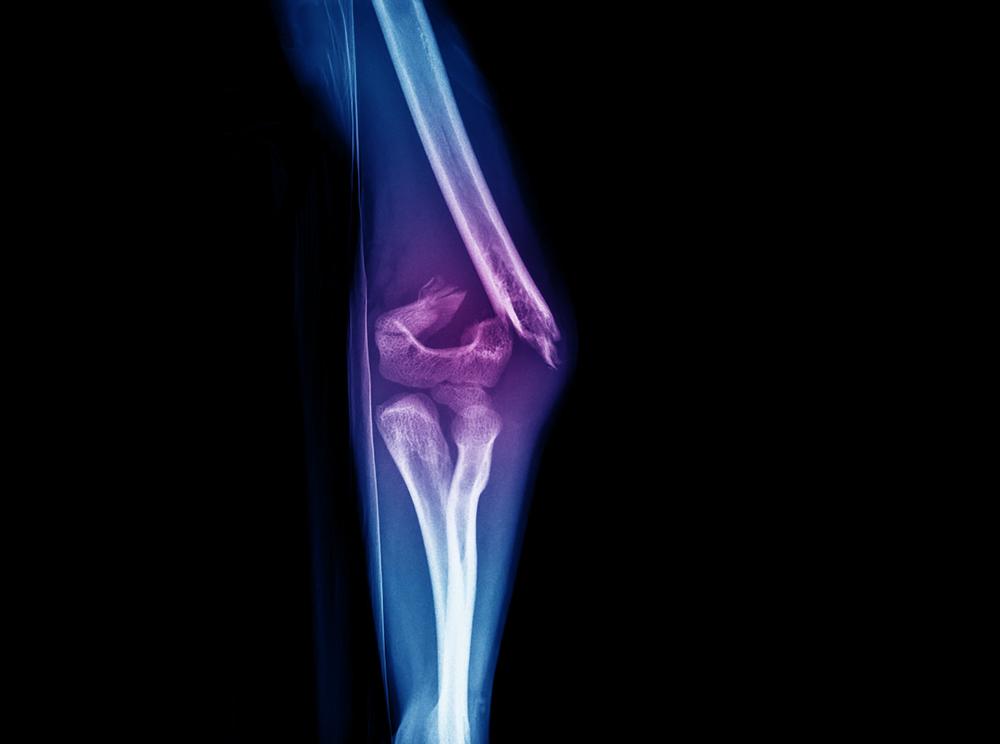

5. Patah tulang tanpa cedera

Tidak hanya menimbulkan nyeri, beberapa pasien juga mengalami patah tulang tanpa cedera terlebih dahulu. Kondisi ini bisa menjadi gejala pertama bahwa Anda menderita kanker, tapi bisa muncul bertahun-tahun setelah pengobatan kanker.

Sarkoma dapat melemahkan tulang dan menimbulkan risiko patah. Biasanya tulang yang patah adalah tulang panjang lengan dan kaki serta tulang belakang.

Seringnya gejala diikuti dengan kelemahan di kaki atau lengan dan tingginya kadar kalsium dalam darah yang dapat menyebabkan mual, muntah, sembelit, dan kebingungan.